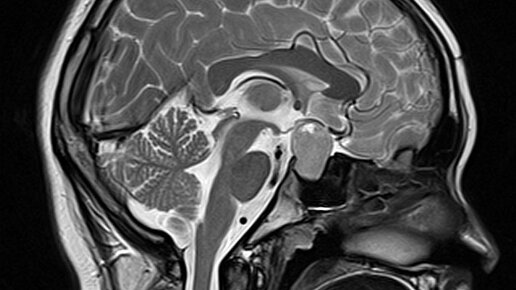

В диагностических центрах МРТ гипофиза используется: ЧТО ТАКОЕ МРТ ГИПОФИЗА МРТ гипофиза – это узконаправленный, прицельный метод диагностики гипофиза и тканей головного мозга, находящихся в зоне турецкого седла. Сложность обнаружения изменений в питуитарной железе способом объясняется его местом нахождения в основании головного мозга и маленькими размерами в диапазоне от 15 до 17 мм. Гипофиз играет важную роль в функционировании эндокринной системы человека. Орган отвечает за выработку гормонов, влияет на рост и обменные процессы в организме человека...

МРТ гипофиза – это наиболее информативный способ для выявления и оценки поражений питуитарной железы, а также окружающих ее тканей в зоне турецкого седла. Данное обследование не следует путать с МРТ головного мозга, где гипофиз тоже визуализируется, но менее четко и прицельно...